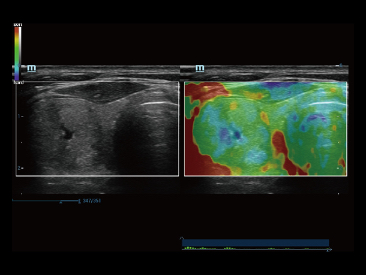

Desde que se fundó la compa?ía, Mindray ha explorado incansablemente nuevas formas de mejorar la confiabilidad del diagnóstico. Con la revolucionaria tecnología de ZONE Sonography?, la nueva plataforma ZST+ de Resona?7 lleva la calidad de la imagen por ecografía a un nivel superior mediante el procesamiento de datos de canal y la adquisición de zona.

Además de la calidad de imagen de primer nivel, Resona?7 también mejora las capacidades de investigación clínica con el revolucionario V?Flow para la evaluación hemodinámica vascular y con la adquisición de planos más inteligente a partir de conjuntos de datos 3D para el diagnóstico del SNC fetal. Al combinar el funcionamiento multitáctil basado en gestos más intuitivo y todas las características clínicas esenciales, Resona?7 realmente lidera las novedades en innovación de ecografías.